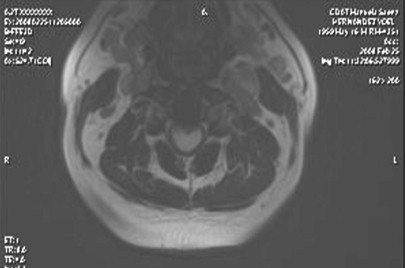

Se realizó estudio de Imágenes por Resonancia Magnética de columna cervical, utilizando un equipo Philips Panorama, abierto, de 0.23 T, realizando secuencias sagitales en T1 y T2 y axiales en B-FFE 3D, donde se observan signos de espondilosis y degeneración discal, complejo disco osteofito a nivel de los espacios intervertebrales C3-C4, hasta C5-C6. Se observa una imagen ocupativa intramedular que provoca ensanchamiento fusiforme de la médula, ocupando la mayor parte del diámetro de la misma y extendiéndose por varios segmentos medulares (desde C3 hasta el espacio intervertebral C6-C7), la cual se muestra hipointensa en T1 e hiperintensa en T2 sin calcificaciones ni otras alteraciones en la intensidad de señales, estando en relación por sus características con un TU (astrocitoma).

Los Astrocitomas son tumores medulares menos frecuentes que el ependimoma. Pueden afectar cualquier localización con predilección en la región cervical y dorsal. Casi todos se extienden en sentido longitudinal por lo que afecta varios segmentos y a veces puede comprometer a la totalidad de la médula.

Todos los astrocitomas medulares son infiltrantes y de crecimiento lento con bajo grado de malignidad, comparado con los tumores cerebrales. Los límites son mal definidos y de naturaleza progresiva, por lo que en la mayoría no suele ser posible su extirpación completa y curativa. Alrededor del 15% de los astrocitomas medulares son malignos y pueden producir metástasis. Es frecuente la formación de quistes intratumorales y a menudo se observa una siringomielia asociada.

La radiografía simple suele ser normal, en pocos casos se puede observar un aumento de la distancia interpedicular. La mielografía muestra un ensanchamiento medular inespecífico y multisegmentario. La resonancia magnética es actualmente el procedimiento para la evaluación de tumores espinales. Los astrocitomas son iso a ligeramente hipointensos en T1 e hiperintensos de T2; con el contraste todos realzan las imágenes.